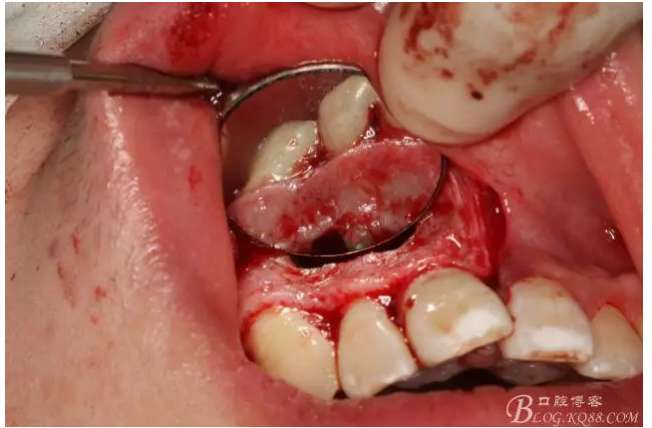

圖4.摘除囊壁后形成的巨大骨腔

圖5.清理骨腔,可以看到12的根尖暴露在骨腔內(nèi)。